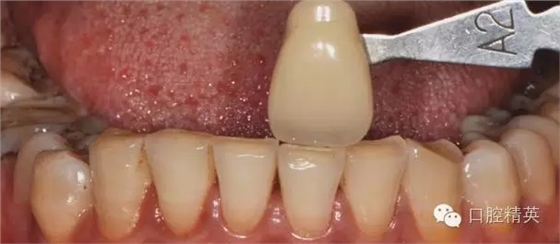

術(shù)前比色

640.webp (9).jpg